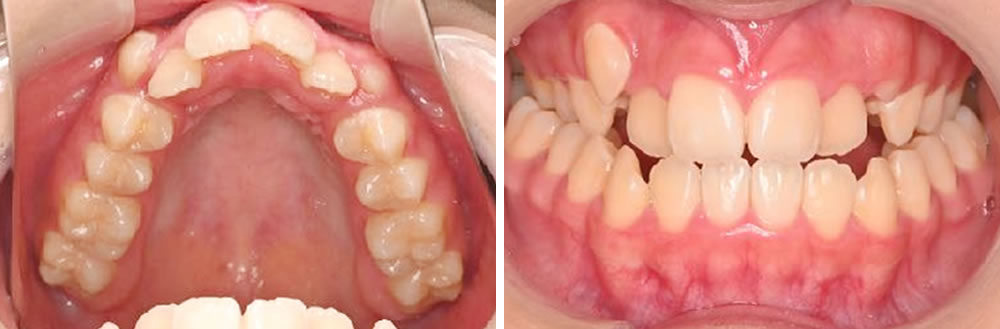

上の犬歯が出ているのと全体的な歯並び、噛み合わせが気になるとの主訴で来院された患者さまです。

CT画像、模型分析、口蓋形態の検査などを行い、患者様の上顎歯列は、歯列だけを広げるのではなく、骨から広げる必要があることが分かりました。

本症例では、マルチブラケット装置によるワイヤー矯正と上顎の歯列を骨から拡大する装置【急速拡大装置(RPE)】を併用し、上顎を広げることで犬歯の生える場所を獲得し、噛み合わせを改善していくという治療方針を立てました。

【初診時】